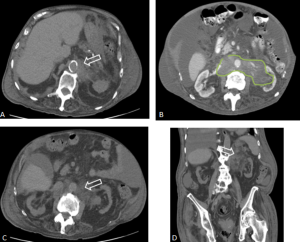

Retroperitoneal and renal involvement occurs in a significant proportion, with CT and MRI demonstrating bilateral perinephric and posterior pararenal soft-tissue infiltration, producing the classic “hairy kidney” appearance. Infiltrates are generally isoattenuating or iso- to hypointense to skeletal muscle with mild contrast enhancement; FDG uptake may be present but can be obscured by physiological renal activity. Chronic infiltration may result in renal atrophy.

Although both ECD and retroperitoneal fibrosis can lead to hydronephrosis, their distribution differs: ECD typically affects the perinephric fat and renal hila, whereas idiopathic RPF encases the anterolateral aorta and proximal ureters. Aortic encasement (“floating aorta sign”) and periureteric involvement may occur, but ECD usually spares the IVC and pelvic ureters. Additional distinguishing features include irregular perirenal infiltration and bilateral symmetric adrenal thickening.